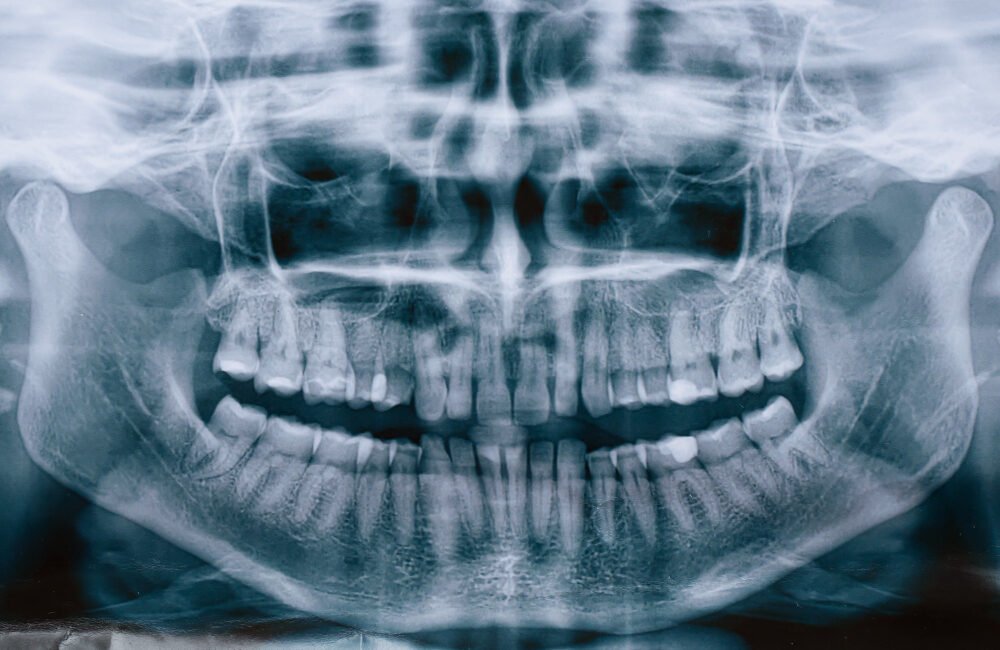

Panorámica Dental

Imagen completa de toda la boca en una sola toma, ideal para diagnósticos generales.

Permite evaluar:

Dientes completos

Muelas del juicio

Hueso maxilar y mandibular

Infecciones o anomalías